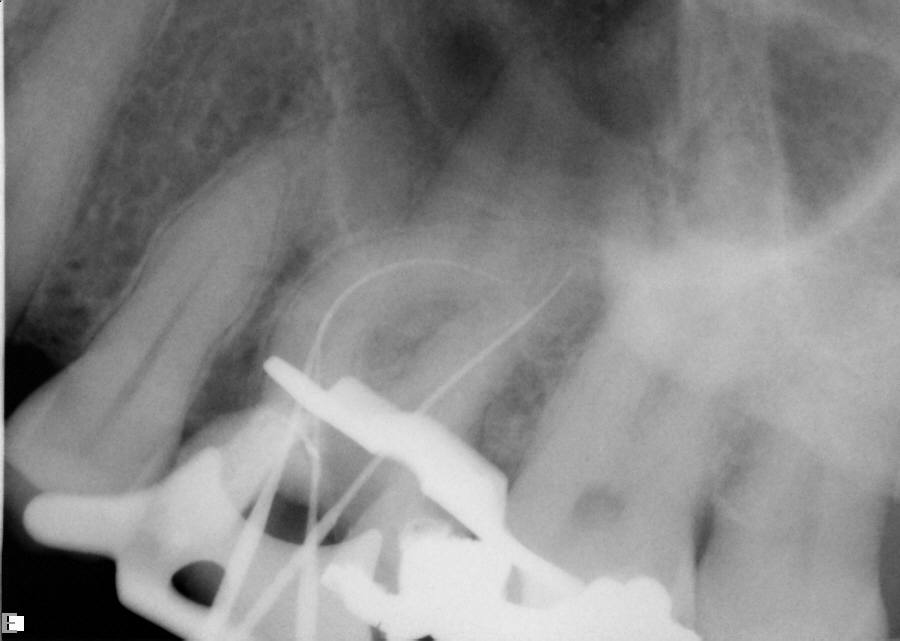

The question remains: how often should clinicians use apex locators, and are they really necessary? Because studies have shown them to be up to 96% accurate,8 it stands to reason that they could be used in every case possible. In some instances, the apex cannot even be seen radiographically. In these cases, using an apex locator is imperative to finding the true working length of the canals. The question remains: how often should clinicians use apex locators, and are they really necessary? Because studies have shown them to be up to 96% accurate,8 it stands to reason that they could be used in every case possible. In some instances, the apex cannot even be seen radiographically. In these cases, using an apex locator is imperative to finding the true working length of the canals. Figure 10 and Figure 11 through Figure 14 demonstrate two such cases; they likely would not have been successfully completed without the use of an apex locator. Even the final PA (Figure 14) does not clearly depict where the canals end.

Working films or radiographs, however, should not be completely eliminated from the clinician’s armamentarium. While practitioners may legally only be required to depict a preoperative and postoperative radiograph, from an endodontic point of view at least one working radiograph should always be taken. This does not mean that a master file radiograph has to be taken; however, it is prudent to take one in cases in which the anatomy is challenging, and the author recommends always taking a master cone radiograph (Figure 11 through Figure 14).

The master cone PA is the last indicator clinicians have in assessing whether or not their working lengths were truly accurate. This radiograph is crucial in affording the practitioner the opportunity to make adjustments to properly complete the procedure to the desirable lengths. An example is presented in Figure 15 through Figure 18. Figure 16 and Figure 17 show a master cone PA that demonstrates two of four canals to proper length. After adjusting the length of the other two master cones, the clinician was able to correct the lengths to produce a more appropriate result, as seen in Figure 18.